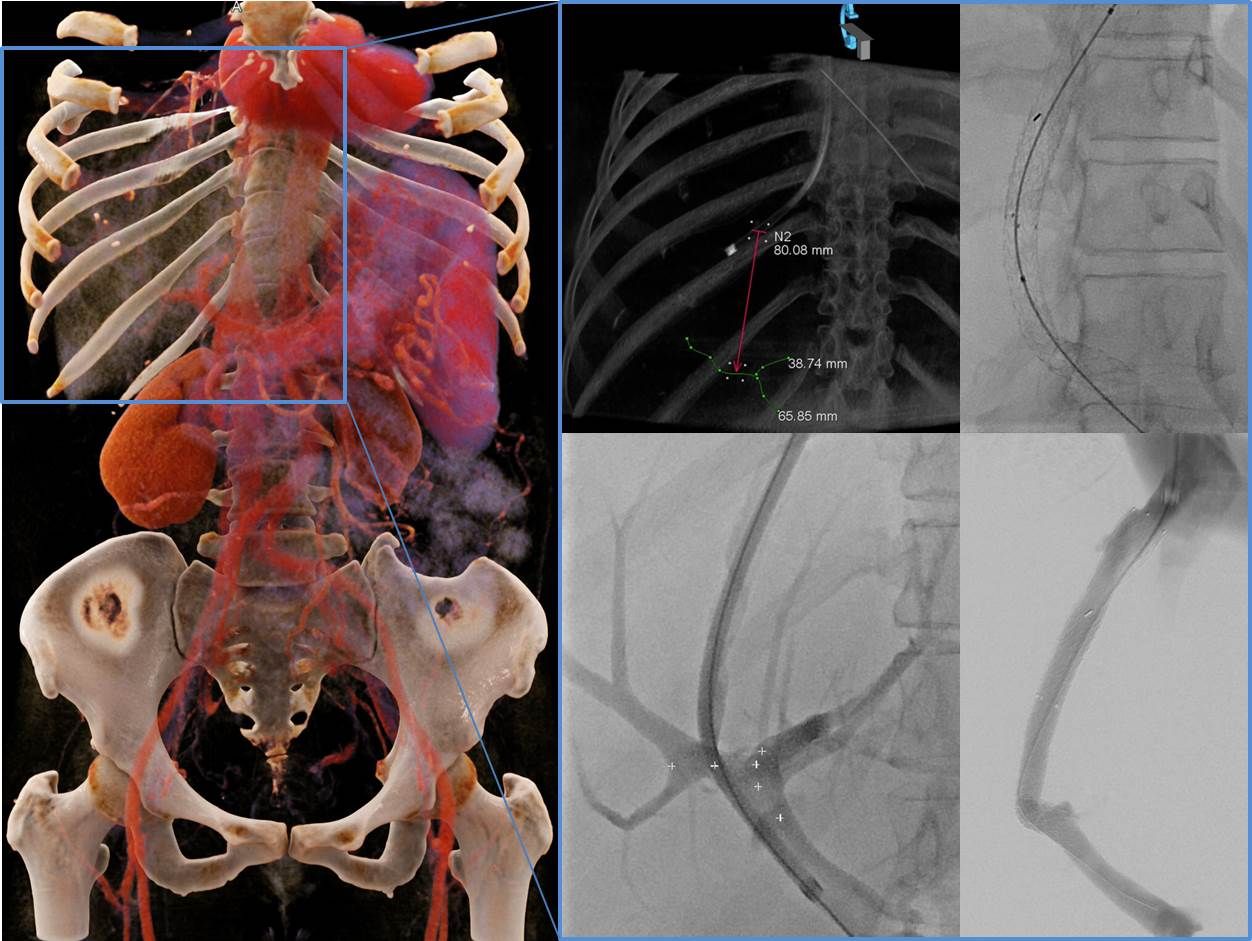

Planung und Durchführung einer TIPSS Anlage.

Im Rahmen einer transjugulären intrahepatischen portosystemischen Stent Shunt (TIPSS)-Anlage wird eine intrahepatische Kurzschlussverbindung zwischen einer Lebervene und einem Ast der Pfortader erstellt. Der TIPSS ist die erfolgreichste Methode, um einen erhöhten Pfortaderdruck zu reduzieren und so die Symptome einer Leberzirrhose wie Aszites (Bauchwasser) oder Varizen (Umgehungskreisläufe) zu behandeln. Ein TIPSS hat sich auch bei der Therapie seltener Erkrankungen wie einer Pfortader-Thrombose oder einem Budd-Chiari-Syndrom bewährt.

Unser Zentrum zeichnet sich weiterhin durch eine dreidimensionale bzw. räumliche periprozedurale Planung der TIPSS Anlage aus, welche ein insgesamt schonenderes Vorgehen mit verbesserten Ergebnissen ermöglicht.